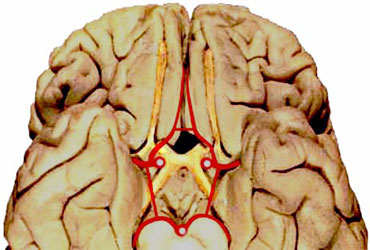

* Le cadre artriel ainsi constitu est interpos entre le pourtour de la selle turcique et la base du diencphale circonscrite par le losange opto-pdonculaire.

Polygone de Willis trac autour du losange opto-pdonculaire

Aspect ventral du tronc crbral et du losange opto-pdonculaire

-aci: artre crbelleuse postro-inf.

-acm: artre crbelleuse moy.

-acp: artre crbrale post.

-acs: artre crbelleuse sup.

-ap: artres pontiques

-asa:artre spinale ant.

-av: artre vertbrale

-ci: carotide interne

-cp: communicante post.

Le polygone baigne dans l'espace sous-arachnodien que constitue la citerne opto-chiasmatique. Les communicantes postrieures reposent sur les lames dure-mriennes reliant les apophyses clinodes de chaque ct.